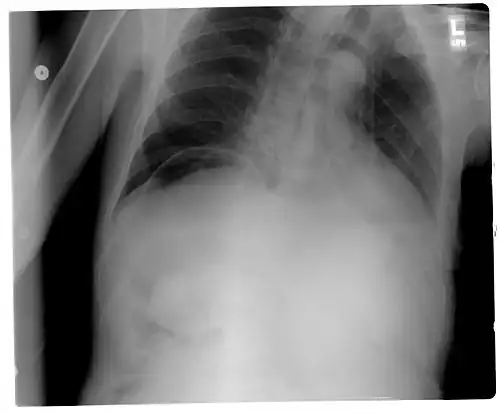

Pneumoperitoneum seen on X-ray with the patient lying on his left side. -

When present, pneumoperitoneum can be seen on projectional radiography, but small amounts are often missed, and CT scan is nowadays regarded as a criterion standard in the assessment of a pneumoperitoneum.[18] CT can visualize quantities as small as 5 cm3 of air or gas.

Signs that can be seen on projectional radiography are shown below: